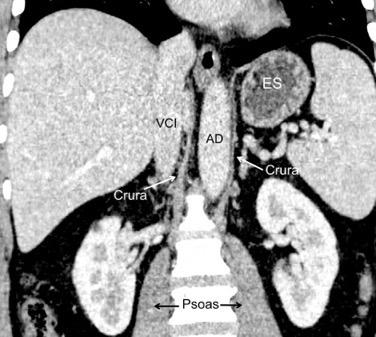

Parte lumbar: 1.Ligamentos arcuatos medial y lateral

2. Cruras conectadas a vértebras lumbares y discos. L1-3 a la dcha. L1-2 a la izda.

Cruras conectadas por encima del tronco celíaco por ligamento fibroso arcuato medial. Panicek DM et al. Radiographics. 1998

Las fibras más bajas de las cruras se funden con las de las vainas de los músculos psoas, acotando un espacio llamado “Espacio abierto de la vaina del psoas”, que comunica las cavidades torácica y abdominal.

Panda A et al. “Straddling Across Boundaries”. Thoracoabdominal Lesions: Spectrum and Pattern Approach. Curr Probl Diagn Radiol, 2015 /Restrepo CS et al. The diaphragmatic crura and retrocrural space: normal imaging appearance, variants, and pathologic conditions. Radiographics 2008